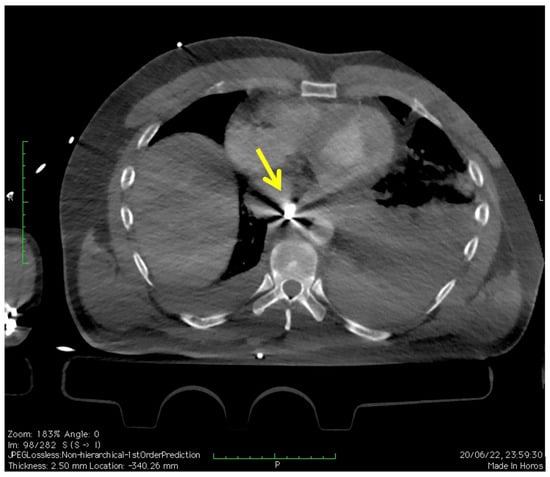

2. Case Presentation